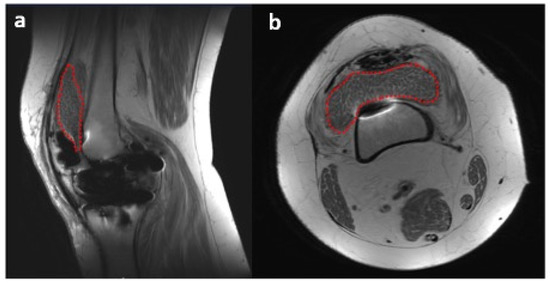

There were no systemic symptoms indicative of infection such as a history of fever or chills. An examination revealed an antalgic gait, diffuse moderate knee swelling with associated warmth, a range of motion of 0 to 100° flexion without an extension lag, no ligamentous instability, and a neutral limb alignment. Her laboratory values were as follows: erythrocyte sedimentation rate (ESR) 124 mm/h (reference range 0–20 mm/h), C-reactive protein (CRP) 17.7 mg/dL (reference range: 0.0–1.0 mg/dL). A knee aspiration was performed, which demonstrated 25 mL of straw-colored native fluid, 77% neutrophils, and negative cultures after 14 days. NexGen sequencing (MicroGenDx, Orange Country, FL, USA) was also performed on a second aspiration, and the aspiration was also negative for bacterial DNA fragments. The radiographs were normal and showed no evidence of implant loosening (Figure 2). Several aspirations were performed previously that showed no evidence or signs of PJI.

Figure 2. X-rays from 9 September 2022 ((a)—lateral view, (b)—anterior–posterior view, (c)—Merchant view). Right total knee arthroplasty (TKA) was reidentified with components in anatomic alignment without fracture.